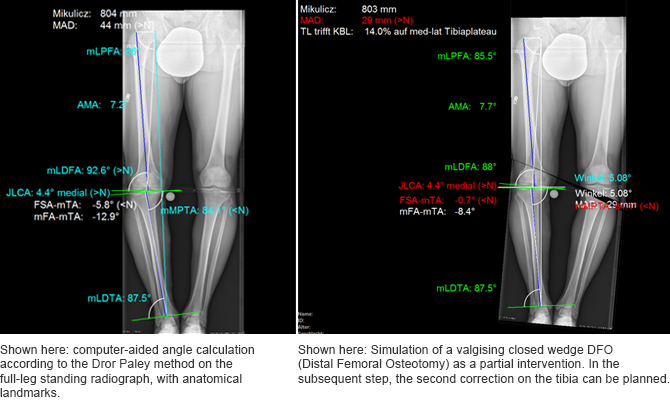

The trauma center in Tübingen is especially fond of the program’s simulation capabilities for corrective osteotomies of deformities. In the past, the axes on the radiograph were measured using a protractor, but now the computer handles this task. It works faster and – more importantly – much more accurately. With a conventional radiograph, analyzing a deformity in detail required a great deal of effort. Only simple methods were available for planning the correction at the tibia head. This resulted in inaccurate planning. But now highly precise planning is possible. Various implants, plates, and angles can be simulated to observe their effects on the geometry of the leg. The surgeon can then compare two or three planning options and choose the most optimal variation for the operation. « The whole process takes maybe a half hour, » according to Dr. Schröter. « This has existed in theory for quite some time, but digital planning now allows us to turn theory into reality. » For osteotomies, correction of collateral ligament instabilities (caused by degraded cartilage, for example) can be simulated. The simulation improves the quality of the operation by accounting for the patient’s individual physiological and anatomical characteristics.

Even joint-specific and nontypical planning, for situations like supramalleolar corrective osteotomies and leg elongations with motorized pins, can be planned and much more. Even more important is simulation of the changes to the joint axes, for example, during distraction.

Clear graphical images

In addition to the many functional benefits, digital planning also saves a tremendous amount of time during day-to-day activities. But automatic documentation of deformity analyses does even more than just save time. It also gives the surgeon the legal security that comes with the ability to objectively and completely track every step. Digital planning is easy to discuss with colleagues and can be used for educational and training purposes. When meeting with the patient, having an easy-to-understand graphical image makes it easier for the patient to understand each step of the operation. « Before » and « After » comparisons allow the surgeon and patient to jointly discuss the operation.